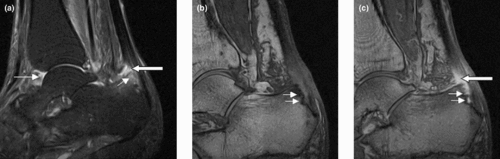

Magnetic resonance images of sacroiliac joints. Shown are T1-weighted semi-coronal magnetic resonance images through the sacroiliac joints (a) before and (b) after intravenous contrast injection. Enhancement is seen at the right sacroiliac joint (arrow, left side of image), indicating active sacroiliitis.